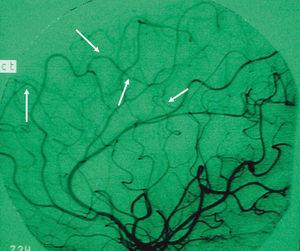

Se trata de una paciente de 14 años con deposiciones mucosanguinolentas de 15 días de evolución y pérdida de 8 kg en el último mes. Analíticamente presenta anemia microcítica, hipoproteinemia, hipoalbuminemia, trombocitosis y marcadores inflamatorios elevados. Los estudios microbiológicos en heces son negativos. A las 24 h del ingreso, coincidiendo con pico febril, presenta disminución brusca de fuerza en hemicuerpo derecho, ataxia y afasia. La TC cerebral muestra lesión hipodensa yuxtacortical en convexidad parietal izquierda sugestiva de lesión isquémica o absceso cerebral, por lo que, ante la duda diagnóstica, se instaura corticoterapia antiedema cerebral y antibioterapia de amplio espectro. La rectoscopia muestra hallazgos sugestivos de proctitis ulcerosa con biopsias compatibles. Tras iniciar el tratamiento anteriormente descrito desaparece la fiebre y mejora la clínica neurológica. Paralelamente presenta mejoría progresiva de la sintomatología digestiva. Para descartar trombosis del seno venoso, se realiza estudio de hipercoagulabilidad (factores V, VII, VIII y X de coagulación, antitrombina III, mutaciones de protrombina, proteínas C y S, homocisteína, anticoagulante lúpico, funcionalismo plaquetario, y anticuerpos anticardiolipina) siendo normal. Dada la mejoría, es dada de alta con corticoides en descenso y mesalazina. Una semana después reingresa por empeoramiento de su clínica digestiva. La colonoscopia realizada es compatible con pancolitis ulcerosa. Al no responder a corticoterapia intravenosa se añade ciclosporina A, lográndose así controlar la situación. La angiorresonancia cerebral realizada muestra disminución de la imagen patológica previa. Dos meses tras el alta y en tratamiento de mantenimiento con azatioprina, presenta crisis convulsiva tónico-clónica generalizada. Una nueva TC cerebral muestra lesiones residuales parietales y nuevas lesiones bilaterales afectando convexidades parietales, sugestivas de infartos. Se solicita arteriografía cerebral que muestra vasculitis de ramas distales de arterias cerebrales anterior y media (fig. 1). Se instaura tratamiento con pulsos mensuales de ciclofosfamida y esteroides orales en dosis decrecientes, asociados a azatioprina, tratamiento anticonvulsivante y profilaxis con heparina y AAS, presentando buena evolución neurológica. Tres meses después reinicia clínica digestiva que no responde a corticoterapia intravenosa, decidiéndose colectomía total e ileostomía. Presenta evolución posquirúrgica satisfactoria, lo que permite la supresión progresiva de su medicación. Una nueva arteriografía 7 meses tras la intervención, muestra desaparición de las imágenes vasculíticas. Actualmente realiza profilaxis con AAS mientras que sangrados esporádicos por el muñón rectal, en espera de la creación del reservorio, se han controlado con mesalazina tópica.

Figura 1. Arteriografía cerebral de la paciente en la que se observan tortuosidades (flechas) sugestivas de vasculitis en las ramas distales de las arterias cerebrales anterior y media.